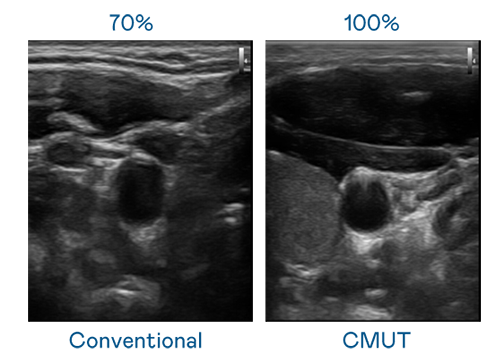

CMUT 技术是一种用电容式微机电元件来产生超音波讯号的技术。与传统 PZT 压电式技术相比,CMUT 频宽增加 30%,更宽频的超音波讯号让影像解析度大幅提升,是实现高影像品质医疗超音波扫描、促进精准医疗发展的关键技术。

超音波影像的解析度高低,首先取决于探头能发出的讯号频宽。AG一飞冲天 CMUT 可提供高清晰的超音波讯号,提供高频宽、高灵敏度、影像纹理细节更高的超音波影像,协助医护人员缩短影像判读时间及利用精准的医疗影像进行诊断。